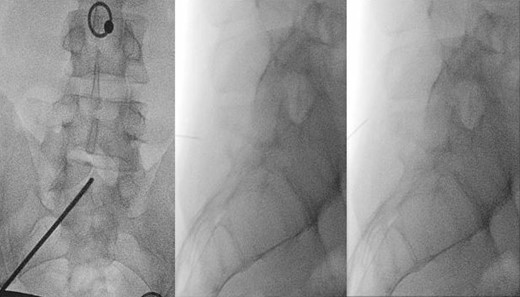

We then performed an infiltration with bupivacaine 0.5% above and below the S1 spinous process, at the level of pressure-evoked pain, with immediate improvement of painful hyperextension, and 8 hours of pain relief (Fig. 4).

Left: localization of pressure-induced pain. Middle and right: under fluoroscopic guidance, S1 perispinous infiltration.